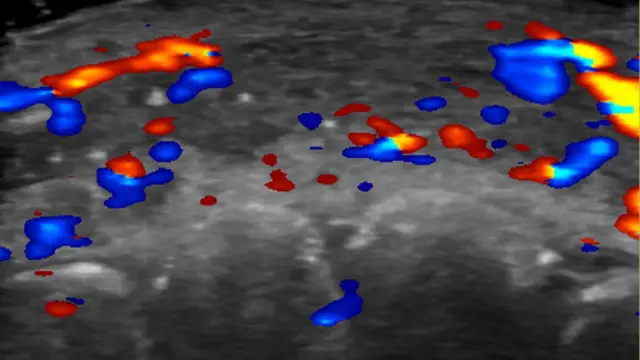

Pesquisadores usaram um ultrassom para estudar 100 casos de preenchimento que deram errado.

Clínicas estão sendo aconselhadas a fazer uma ultrassonografia antes de iniciar o procedimento no rosto, para evitar dandos a artérias próximas.

Em quase metade dos casos avaliados, ultrassonografias mostraram ausência de fluxo sanguíneo em vasos pequenos que conectam artérias superficiais àquelas mais profundas do rosto.

E em um terço dos pacientes, fluxo sanguíneo estava ausente nos principais vasos sanguíneos.

Para evitar complicações, ela aconselha que as clínicas realizem ultrassonografias para planejar onde o produto vai ser injetado.

Se complicações aparecerem, a ultrassonografia pode guiar o tratamento.

“Se os preenchimentos não forem guiados por ultrassonografias, o tratamento é feito apenas com base nos sinais clínicos e o produto é injetado às cegas”, afirma Sigrist.

“Mas se nós temos o ultrassom, podemos tratar o local exato onde as obstruções ocorrem.”